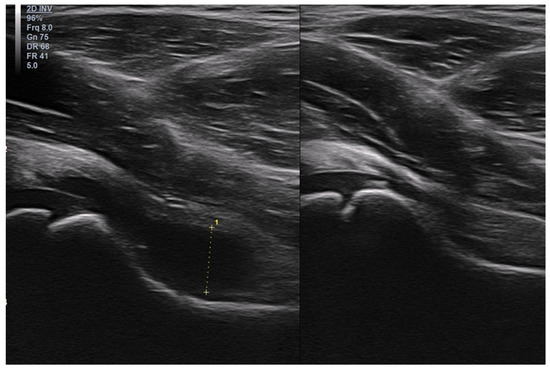

3.2.1. Osteochondritis Dissecans

3.2.2. Osgood–Schlatter Disease